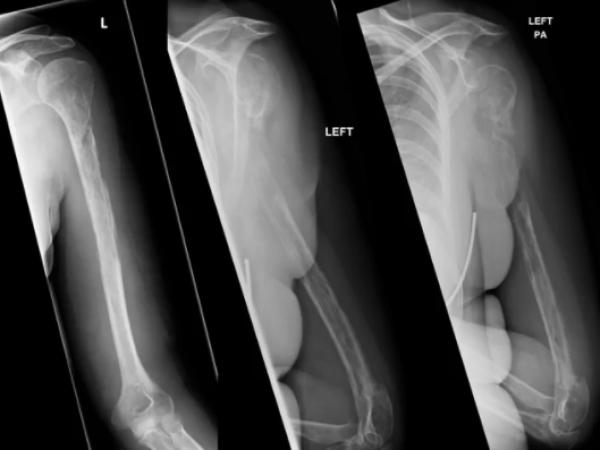

U nizu rendgenskih snimaka, činilo se da kosti ove žene nestaju ljekarima pred očima.

I taj podatak bio je ključan za rešenje misterije, tako bizarne da je cijela Škotska bila na nogama. Žena o kojoj je riječ patila je, ispostavilo se, od Gorham-Stautovog sindroma, odnosno, kako je još zovu "bolesti nestajućih kostiju". U pitanju je ekstremno rijedak fenomen u kome ljudi progresivno i rapidno gube kosti.

Ovaj bizaran slučaj objavljen je krajem marta u izdanju "Journal BMJ Case Reports", a u savremenoj medicinskoj literaturi zabeleženo je samo 64 slična slučaja u celoj istoriji.

Ljekari, inače, ni danas ne znaju šta uzrokuje ovo stanje. Znaju da bolest nije genetska i da je ne uslovljavaju spoljni faktori. Ono što su primijetili kod pacijenata je abnormalno širenje krvnih i limfnih sudova. Oni rastu i šire se tako agresivno da uspijevaju da se infiltriraju u kosti koje se onda lome. Tada benigni, odnosno nekancerogeni tumori krvnih sudova zamijenjuju kost.